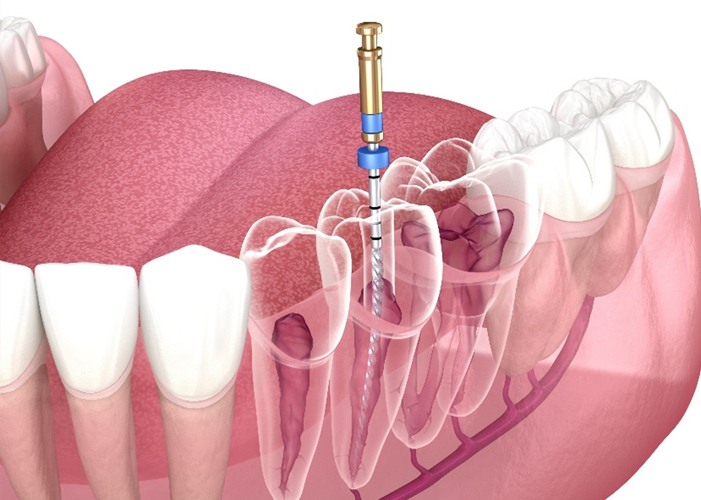

- 일반진료

-

자연치아 보존을 최우선으로 한

기본에 충실한 진료 - READ MORE

- 상악동 거상술+근관치료

- 상·하악 임플란트+근관치료

- 상악동 골이식+근관치료

- 구치부 근관치료+상악동 골이식

- 상악동 거상술+근관치료

- 상·하악 임플란트+근관치료

- 상악동 골이식+근관치료

- 구치부 근관치료+상악동 골이식